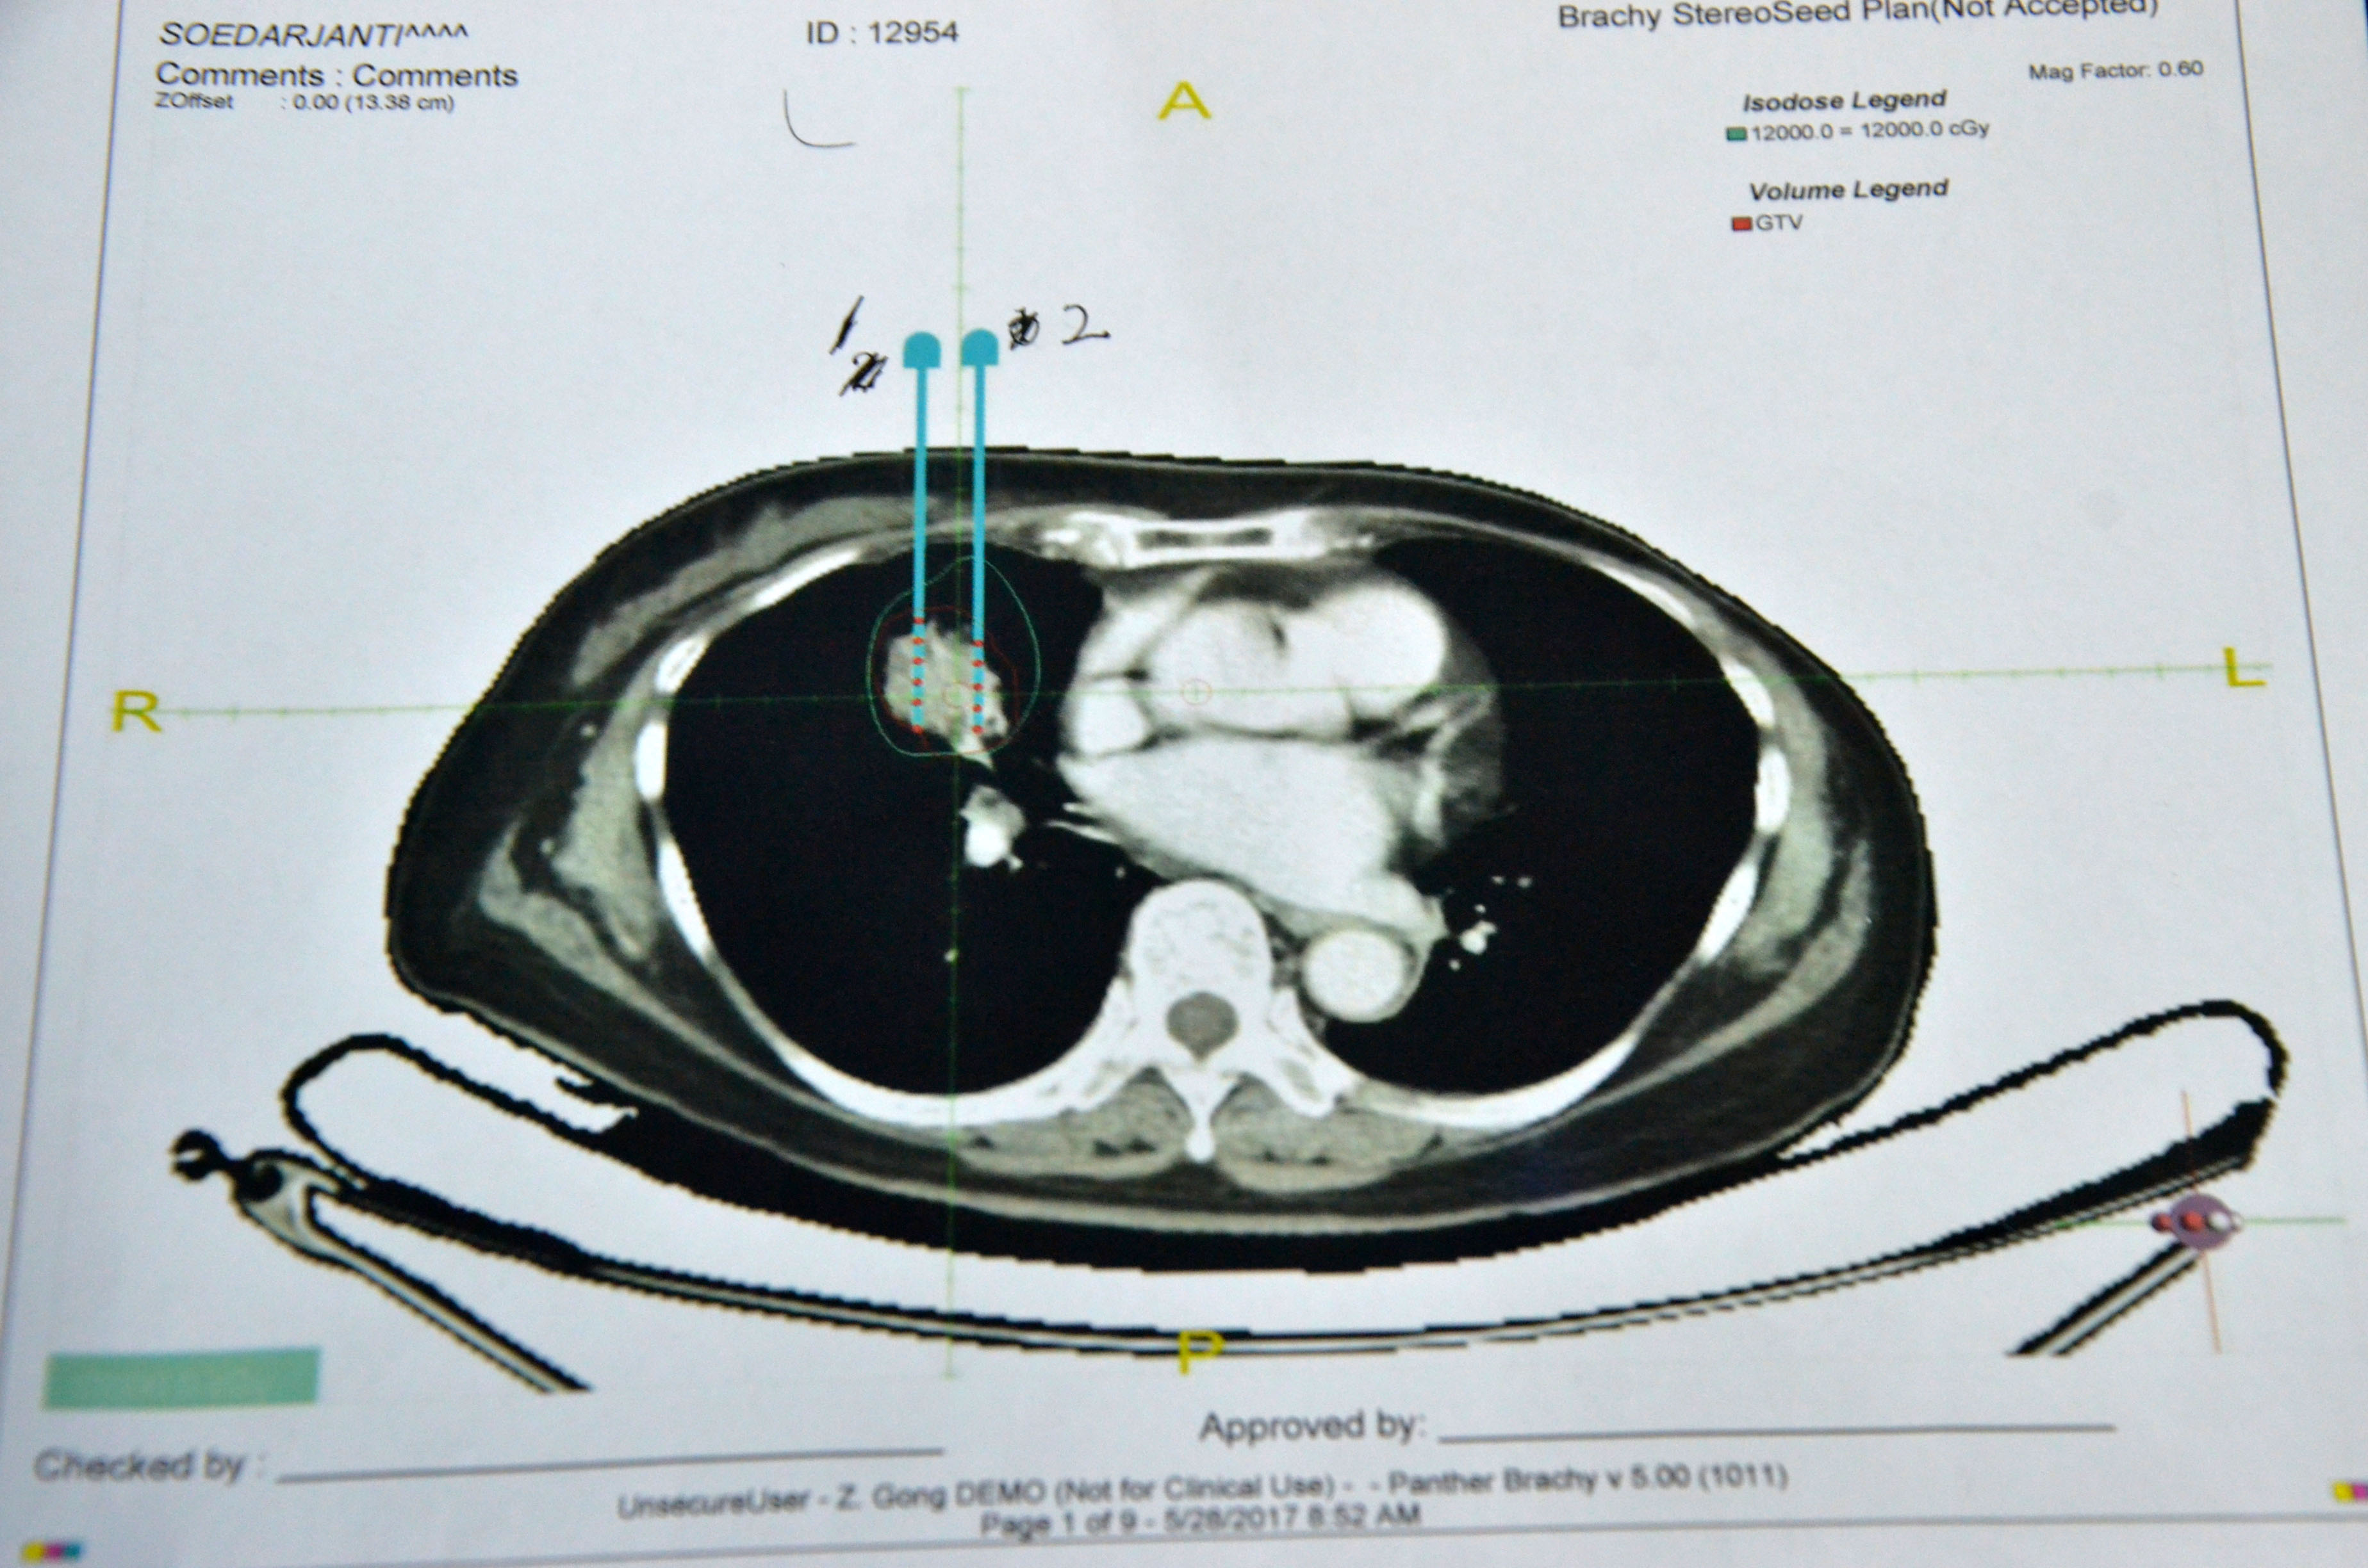

▲術(shù)前計劃

術(shù)前患者進(jìn)行了CT檢查,利用CT進(jìn)行3D建模,通過PROWESS TPS軟件(粒子植入治療計劃系統(tǒng))將患者腫瘤CT掃描圖像進(jìn)行三維重建,完整地呈現(xiàn)出患者皮膚、骨骼、血管和腫瘤之間的關(guān)系。設(shè)計出每一根穿刺針的進(jìn)針路徑、進(jìn)針深度、粒子分布及粒子數(shù)量、腫瘤受輻射的劑量,最后通過3D打印設(shè)備制作出貼合患者皮膚的3D微創(chuàng)導(dǎo)向模板。